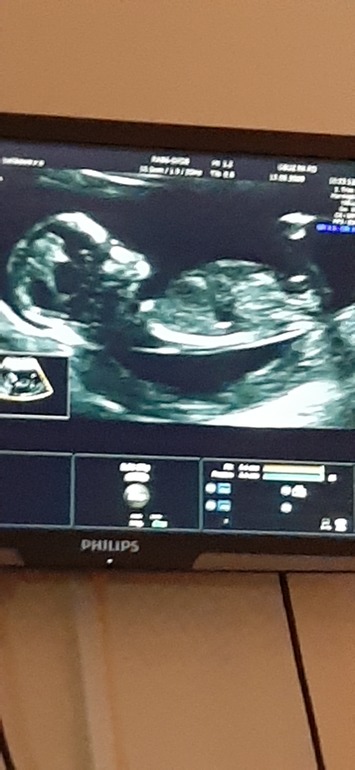

Вопросы про УЗИ, обследования и анализы: что, где, как, когда?Ну вот и прошол 1 скрининг. Узист сказала что девочка. А вам как кажется?

Плоховато видно на фото. По опыту скажу, что в 14.3 тоже была "пупырка" и я отчётливо видела, что что-то торчит, врач долго смотрела и не смогла 100% сказать, только 70девочка/30 мальчик. А в 16ровно уже никаких "пупырок", девочка 100% ;) Если врач опытный, то правильно вам все сказал.

На 1 скрининге пол очень сложно определить. Несмотря на то, что все сформировано, пока достаточно одинаково выглядит. Более точно пол определяют на 2-м. А пока это определение скорее пальцем в небо, хотя не факт, что не угадала)

Вот по положению этой пупырки можно и определить. Под углом 90° вверх-мальчик, параллельно позвоночнику девочка.